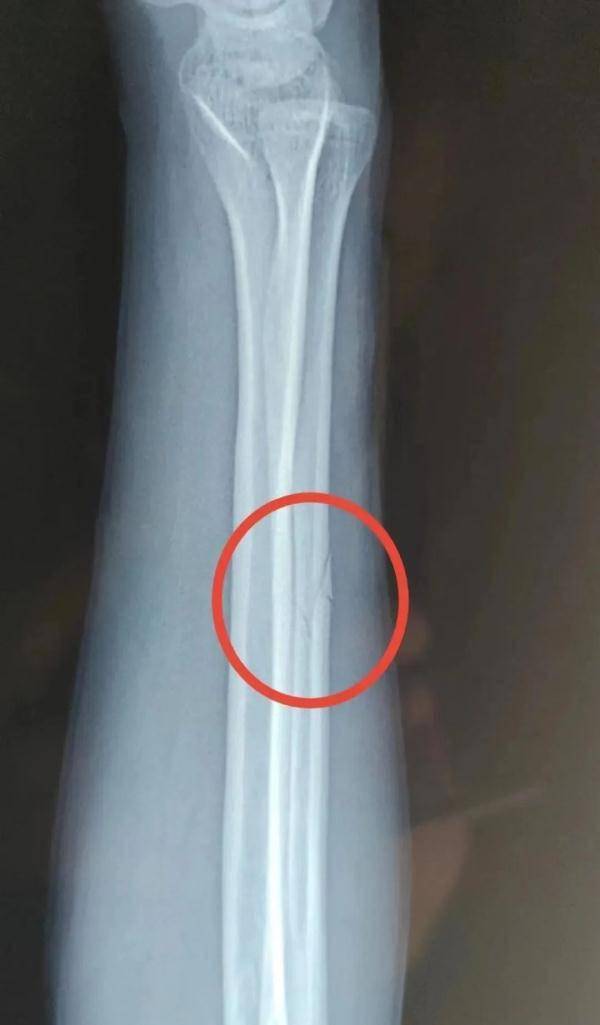

事发后宋某报了警,当晚去医院检查并打了石膏,医生让先回家观察。宋某系第二天右臂痛疼难忍,于2022年11月13日下午6时自行前往丹凤县医院检查。经诊断右尺骨骨折,外伤性头疼。

在宋某出院两个月后,2023年2月13日,商洛市丹凤县公安局龙驹寨派出所向宋某出具了第一次伤情鉴定报告。宋某人体损伤程度属于轻伤二级。

宋某家属并不认可“轻伤二级”的鉴定结果,申请重新鉴定。4月18日宋某拿到了鉴定意见通知书。宋某人体损伤程度属于轻伤一级。